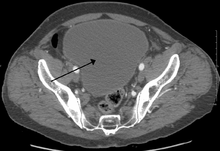

| Urinary retention with greatly enlarged bladder at CT. | |